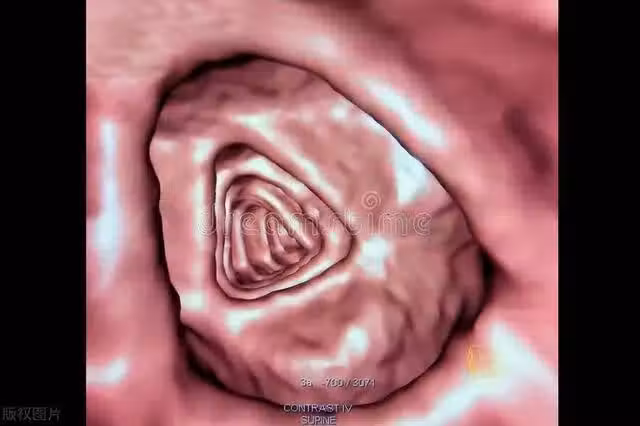

虛擬結腸鏡檢查: 這是一種無需實際內鏡插入的篩查方法,通過計算機斷層掃描來檢查結腸。